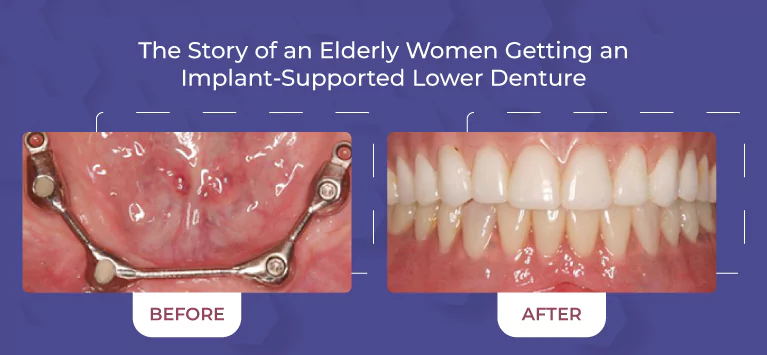

Comprehensive Services

From routine cleanings and preventive care to advanced cosmetic and restorative dentistry, we offer a full range of dental services to keep your smile healthy and vibrant.